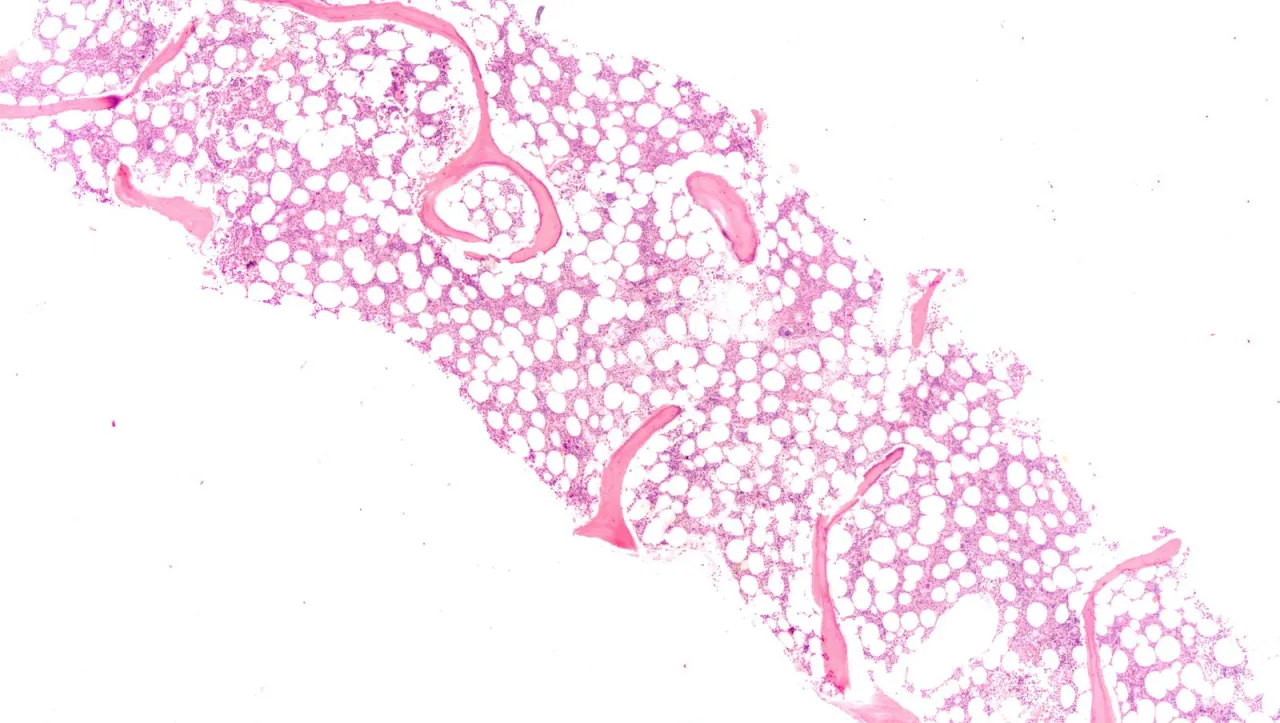

Jedną z poważniejszych przyczyn małopłytkowości jest zajęcie szpiku kostnego przez komórki nowotworowe. W przypadku białaczek, zarówno ostrych szpikowych, jak i limfoblastycznych, nieprawidłowe komórki nowotworowe namnażają się w szpiku, wypierając zdrowe komórki macierzyste odpowiedzialne za produkcję płytek. Podobnie dzieje się w zespołach mielodysplastycznych, gdzie szpik kostny produkuje nieefektywne lub uszkodzone komórki krwi, w tym płytki. Inne choroby szpiku, takie jak niedokrwistość aplastyczna (gdzie szpik jest niewydolny) czy zwłóknienie szpiku (gdzie szpik jest zastępowany tkanką włóknistą), również prowadzą do znacznego upośledzenia produkcji trombocytów.

W wielu przypadkach, zwłaszcza gdy małopłytkowość jest łagodna i ma jasną, przejściową przyczynę (np. po infekcji), leczenie może być prowadzone przez lekarza rodzinnego. Jednakże, w przypadku utrzymującej się małopłytkowości, braku jasnej przyczyny, nasilonych objawów krwotocznych lub podejrzenia poważniejszych schorzeń (takich jak choroby szpiku kostnego czy zaawansowane choroby autoimmunologiczne), konieczna jest konsultacja z hematologiem. Hematolog to specjalista chorób krwi, który ma doświadczenie w diagnostyce i leczeniu małopłytkowości. Może on zlecić dalsze, bardziej specjalistyczne badania, takie jak biopsja szpiku kostnego (pobranie próbki szpiku do analizy), która jest niezbędna do oceny funkcji szpiku i wykluczenia nowotworów krwi.